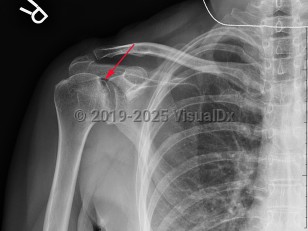

Grade / classification system: Cruess classification

- Stage 1 – normal x-ray, changes on MRI

- Stage 2 – sclerosis and cystic changes, osteopenia on x-ray

- Stage 3 – crescent sign (subchondral fractures) on x-ray

- Stage 4 – flattening and collapse on x-ray

- Stage 5 – degenerative changes extend to the glenoid on x-ray